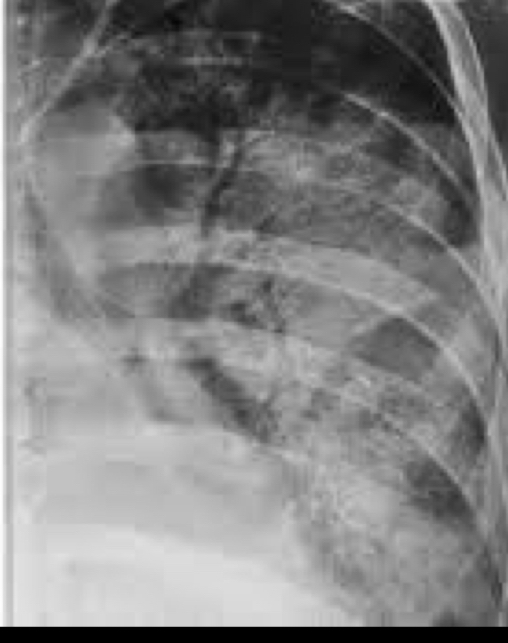

Que patrón pulmonar es

A

Intersticial/reticular